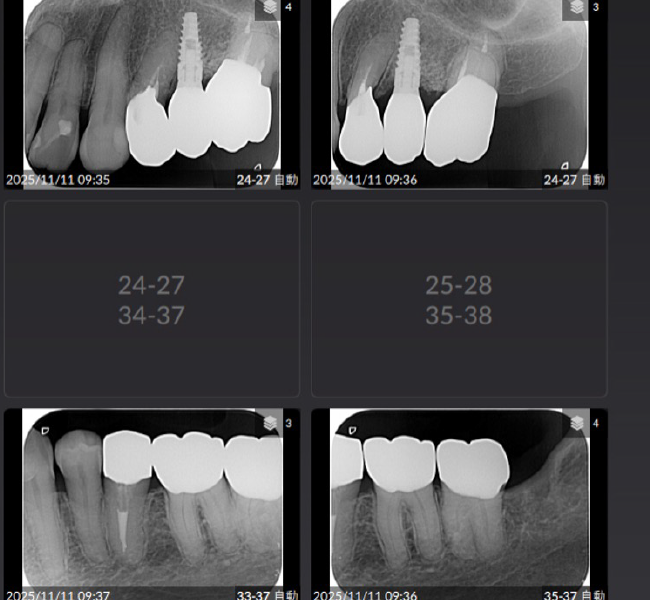

治療前

治療後